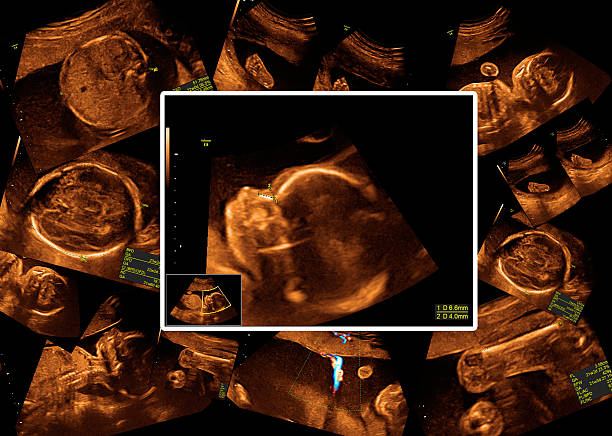

شكل الجنين في الشهر الثالث

بمجرد أن تعلم السيدة بخبر حملها، تبدأ في التساؤل عن كيفية نمو الجنين وشكله وتطوره في داخل بطنها، ومتى ستشعر الأم بالركلة الأولى لجنينها، وعادة ما يكون نمو الأجنة بطريقة يمكن التنبؤ به أسبوع بأسبوع. في هذا المقال سوف نوضح لكِ بالتفصيل شكل الجنين في الشهر الثالث وحجمه ومكانه، وهو الشهر الذي يشهد نهاية الفترة الأكثر أهمية في حياة الجنين، إذ ينتهي معها أغلب أعراض الحمل المزعجة التي عانيتِ منها، مثل القيء وفقدان الشهية والدوار. يكون شكل الجنين في الشهر الثالث أشبه ما يكون بإنسان صغير، وسيكتسب وجهه بعض الملامح المعروفة، كما تكتسب أطرافه طولاً متناسباً مع طول الجسم، وتتكون المعدة والكبد والبنكرياس والطحال والأمعاء والقلب، والجهاز التنفسي يبدأ في النمو. وإذا أردتِ التعرف على المزيد حول حجم الجنين في الشهر الثالث، تابعي معنا حتى نهاية المقال.

قد تتساءل العديد من النساء عن حجم الجنين في الشهر الثالث. يتطور الجنين في الشهر الثالث بشكل سريع، لذلك سوف نوضح التطور في حجم الجنين في الشهر الثالث حسب الأسابيع، ففي الأسبوع التاسع، يصبح طول الجنين 5,5 سم من قمة الرأس إلى العقب، والوزن 10 جرامات، ولا زال المنخران مقفلين، مع ظهور البراعم الأولى لحاستي الذوق والشم، والأجفان تغطي العينين بشكل تام. و خلال الأسبوع العاشر، يبلغ طول الجنين 7,5 سم والوزن 18 جراماً، ويصبح قادراً على الحركة، على الرغم من أنها بطيئة جداً، كما تظهر بصيلات الشعر على الرأس والجلد، مع ظهور براعم الأسنان الدائمة تحت أسنان الحليب، ويصبح الكبد أكبر حجماً، ثم في الأسبوع الحادي عشر تتكون العظام الأولى للجنين، تظهر أولاً في الأطراف على شكل نسيج غضروفي لا يلبث أن يغتني بالخلايا العظمية، ويصبح أكثر تماسكاً وكثافةً، وكذلك تتكون أجزاء غضروفية بالجمجمة والوجه، ويكتمل الأنف ويرتسم الذقن. يواصل العمود الفقري تدعيم بنيته فتنطلق منه بدايات الأضلاع، فيما ترتسم عظام الحوض، ولا يكتمل الهيكل العظمي بمجموع عظامه البالغ 110 عظمة إلا في مرحلة المراهقة. بهذا نكون قد أجبنا على التساؤلات حول حجم الجنين في الشهر الثالث.